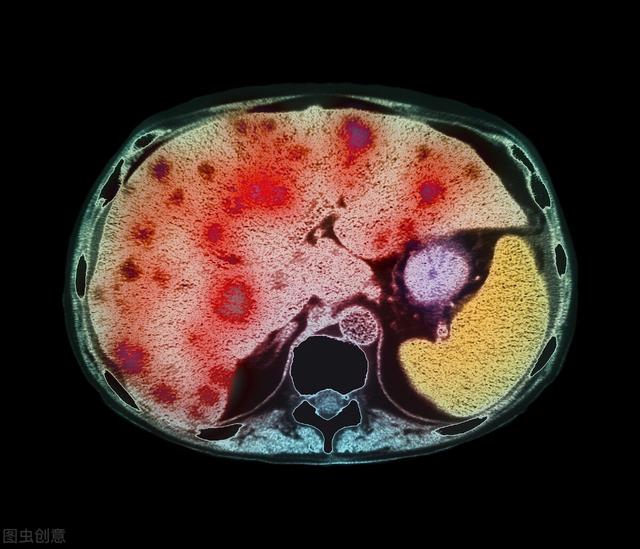

由肝脏引起的肝源性疾病因肝功能受损和门静脉高压导致液体积聚在腹腔内,而形成腹水,是肝硬化最常见的并发症之一,常见于肝硬化失代偿期、肝衰竭、肝脏血管类疾病、自身免疫性肝病、肝病肿瘤等。

一旦患者开始出现肝腹水,就代表肝病已经很严重了。当肝脏受损加重,代谢能力下降,就会使体内的腹水增多。作为正常健康的人,腹腔内的体液其实都会被代谢掉,剩下的不多,如果增多就会形成腹水,由肝脏受损引起的就是肝腹水,这时候一定要尽快就医,避免肝病进一步恶化。

早期的肝硬化患者并不会出现腹水,一旦腹水形成,就表示患者已经进入肝硬化失代偿期,多处于晚期症状了。不仅影响肠胃功能,也会伴有腹痛、排尿次数减少,大便异常,还会有畏寒、低热等状况。

不过,肝硬化引起的肝腹水患者,在腹水形成后,1年死亡风险在15%左右,5年内的病死率则高达44%。